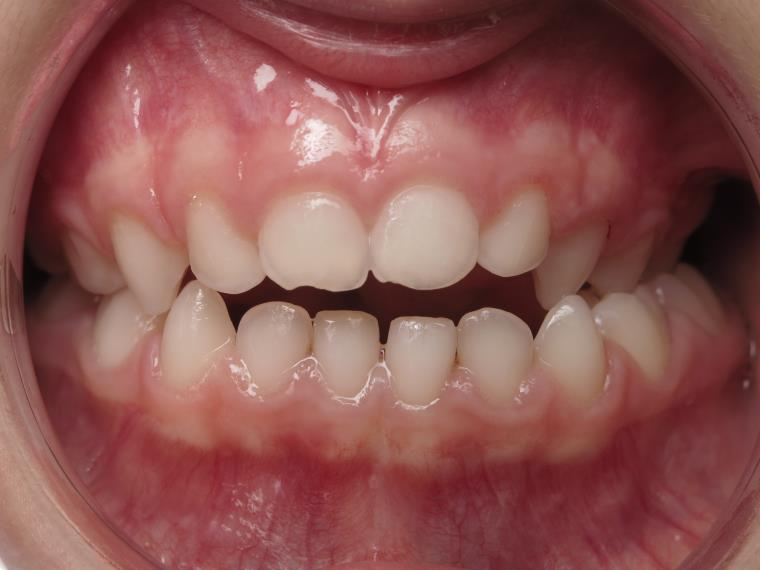

Sélectionnez les différentes étapes du traitement pour comparer et analyser la dentition du cas clinique.

appareillage mobile pendant 5 mois

surveillance évolution de la dentition pendant 27 mois